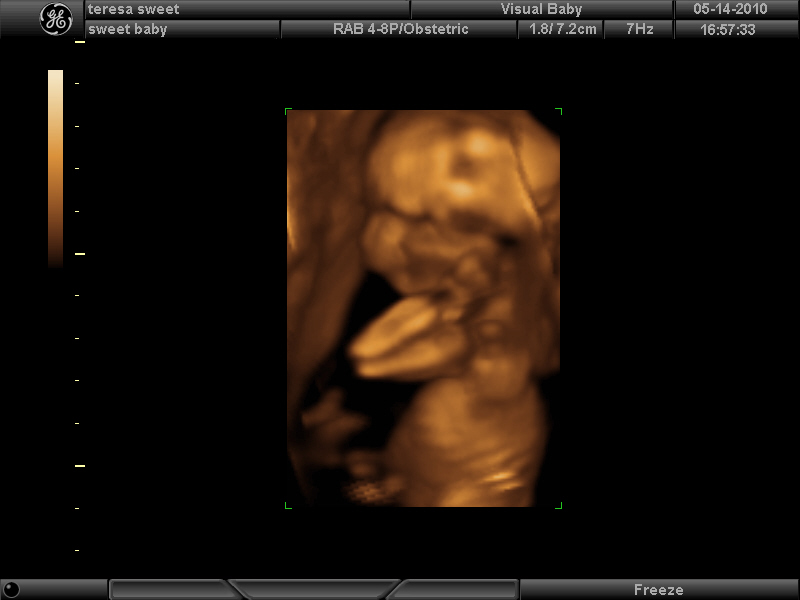

So baby was very very stubborn. Sleeping at first, cord between its legs, not moving much, curled up in a ball, etc etc. lol

Here’s a few photos in 3D. I’m 17 wks now.